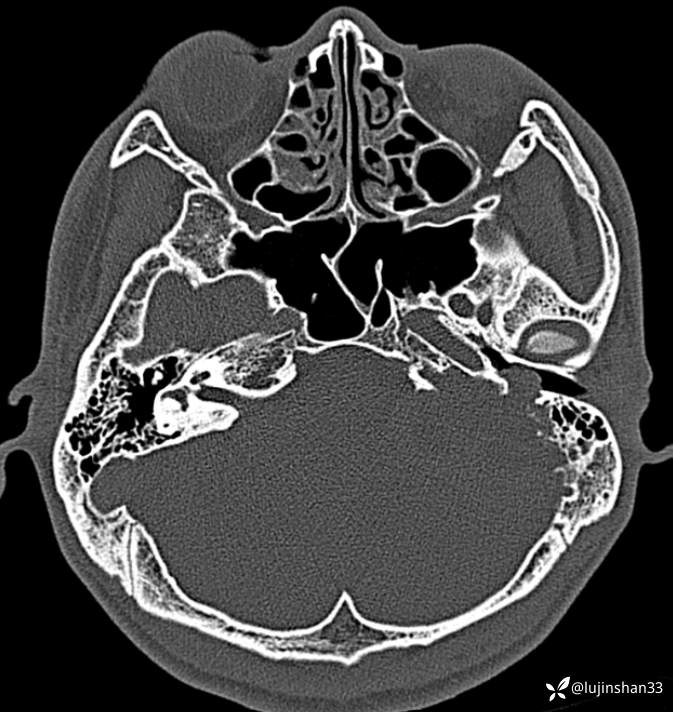

首次术前CT: